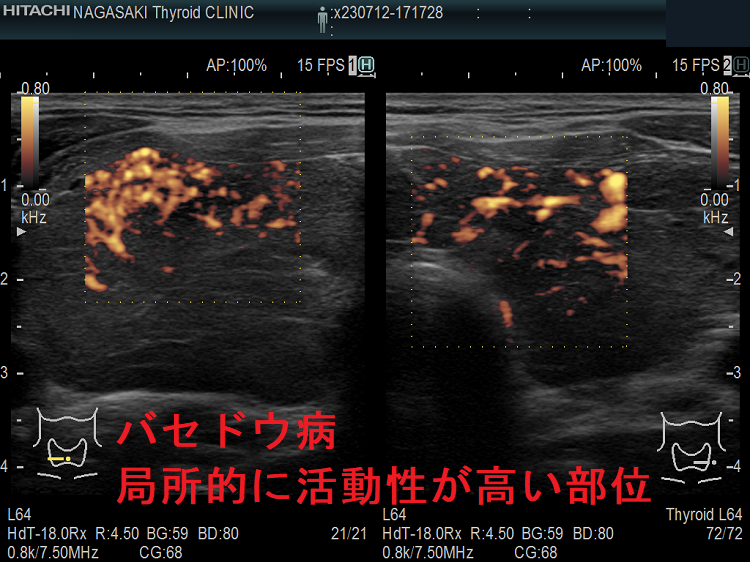

局所的に血流が多く、低エコーな領域

抗甲状腺薬投与により、甲状腺機能が正常に保たれているバセドウ病では、治療前の”火炎状血流増加”と呼ばれる甲状腺内部の異常血流増加が減少していきます。しかし、局所的に血流が多く、低エコーな領域は活動性が残存しています。(J Clin Ultrasound. 2005 Oct;33(8):381-5. doi: 10.1002/jcu.20157.)(Exp Clin Endocrinol Diabetes. 2013 Jan;121(1):1-5.)(AJR Am J Roentgenol. 1996 Jan;166(1):203-7.)

局所的に血流が多く、低エコーでバセドウ病の活動性が高い領域

局所的に血流が多く、低エコーでバセドウ病の活動性が高い領域  ドプラーモード

バセドウ病 局所的に活動性が高い部位

バセドウ病 局所的に活動性が高い部位(低エコー)

バセドウ病 局所的に活動性が高い部位 ドプラーモード

バセドウ病 局所的に活動性が高い部位 ドプラーモード(低エコー領域は局所的に血流が多く)